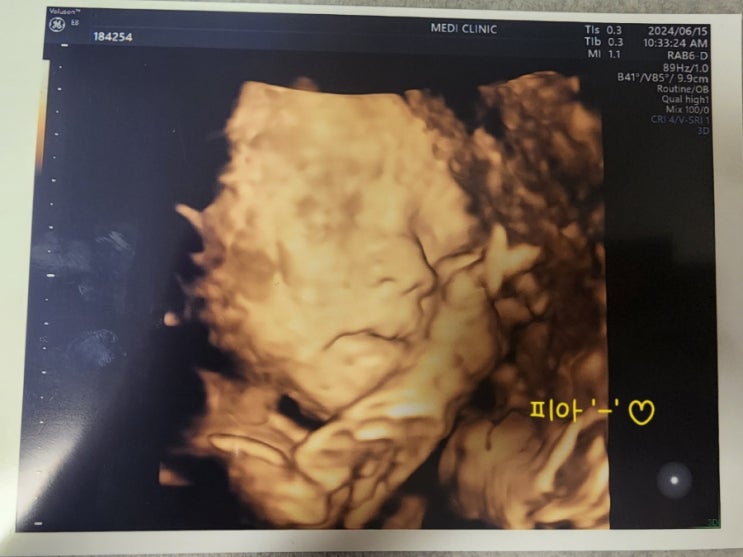

원더맘스 산모교실

무거운 몸 이끌고 원더맘스 산모교실 댕겨옴 자세한 후기는 언젠가 수정을..